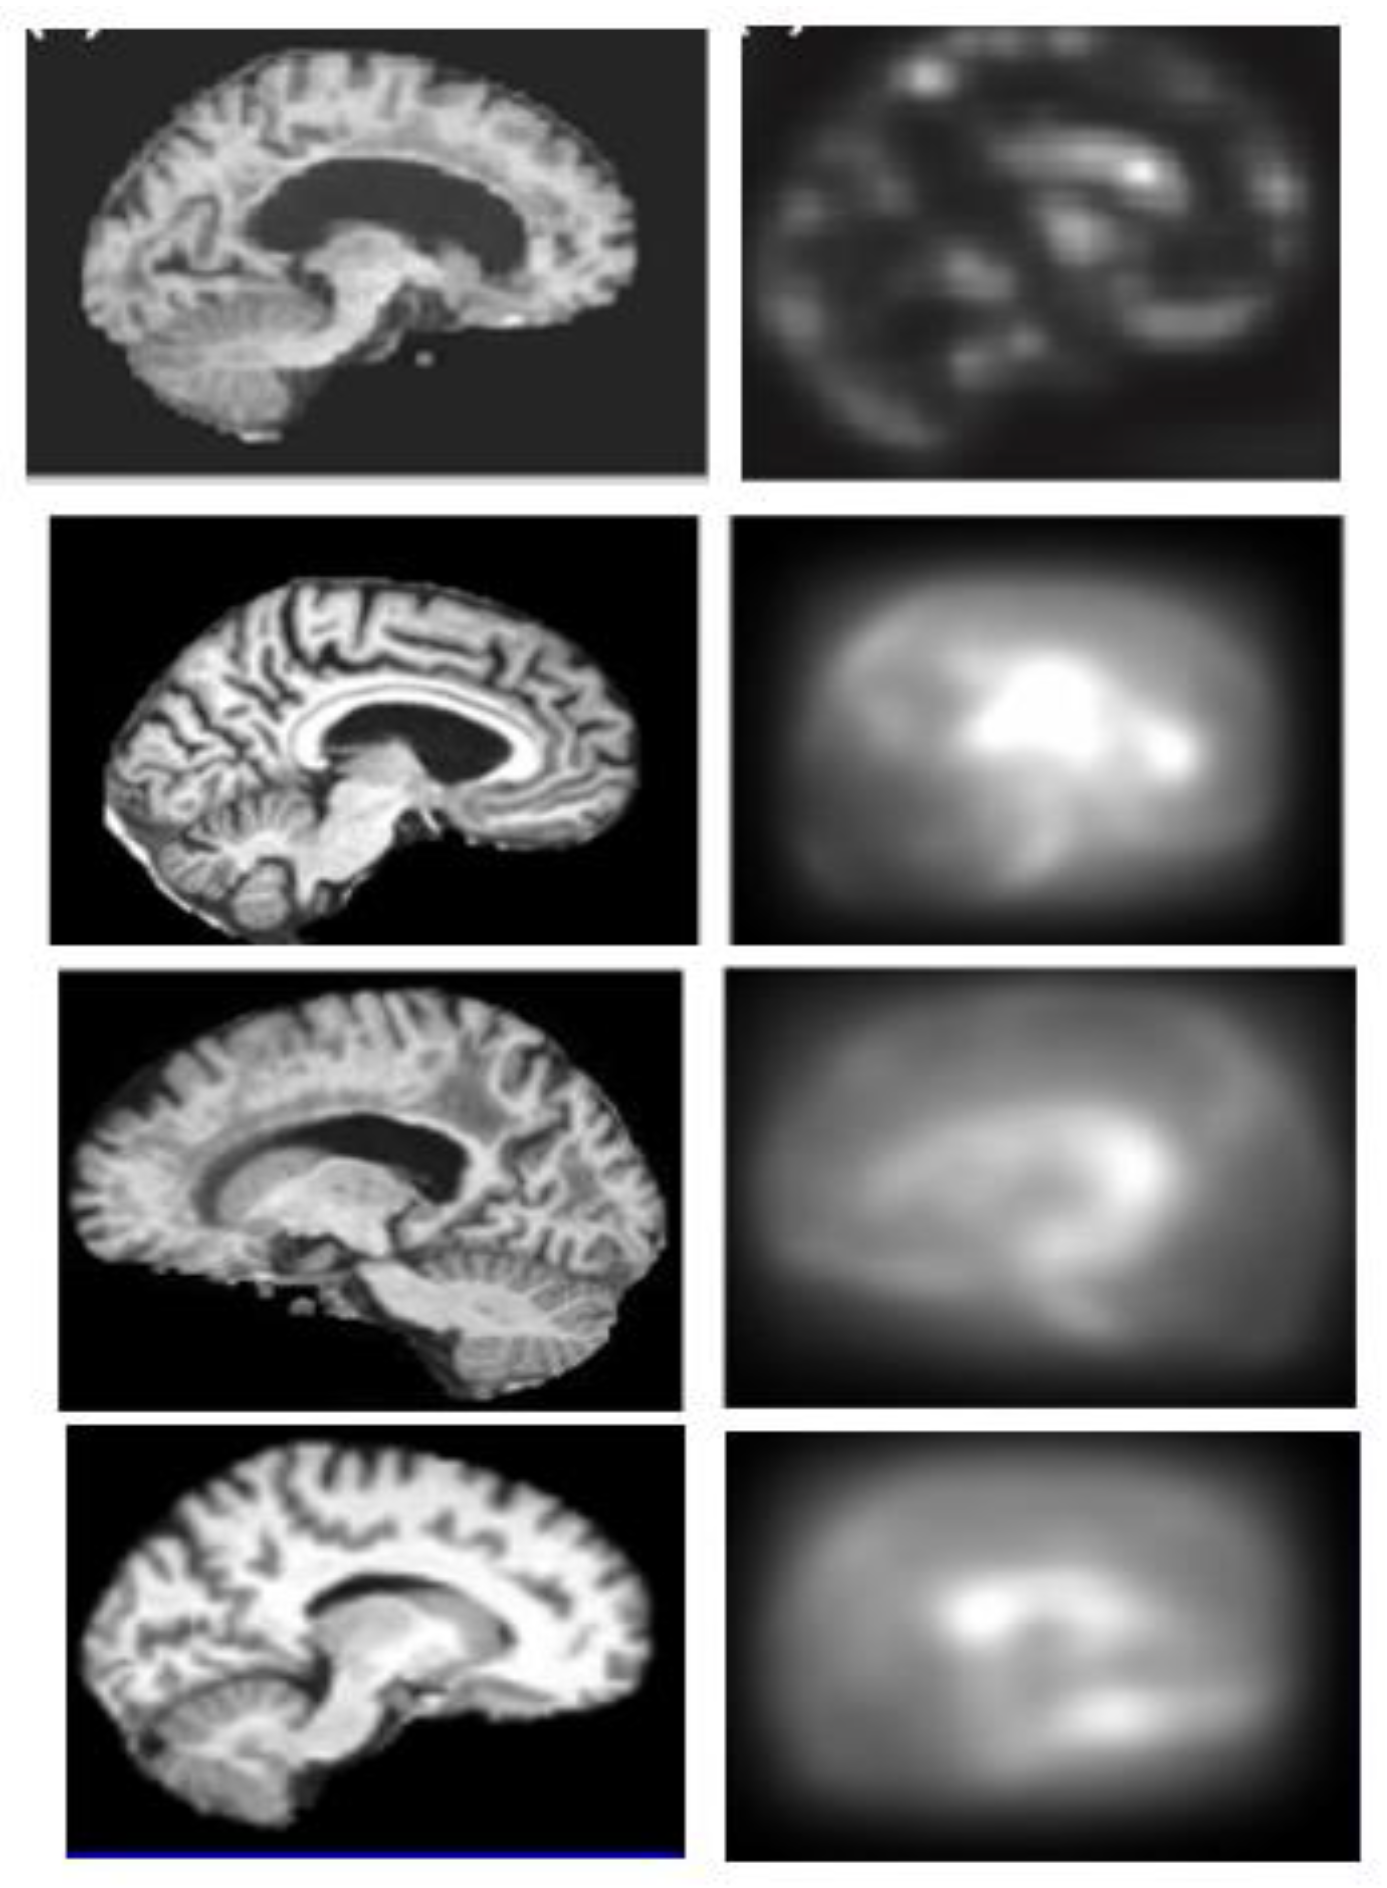

2.3. Generation of Saliency Maps

2.3.1. Top-Down Saliency Maps (

2.3.2. Bottom-Up Saliency Maps (

2.3.3. Final Saliency Map